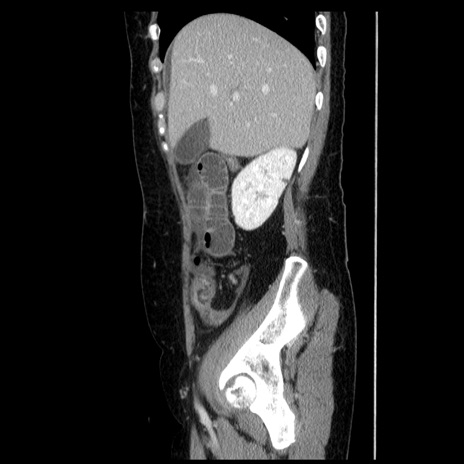

冠状断像

【症例】50歳代女性

【主訴】下腹部痛

【既往歴】卵巣癌術後(8年前に当院で卵巣摘出)

【身体所見】 意識清明、腹部:平坦、腸蠕動音→、やや硬、下腹部自発痛・圧痛あり、反跳痛あり、筋性防御なし。

【データ】WBC 16000、CRP 0.01